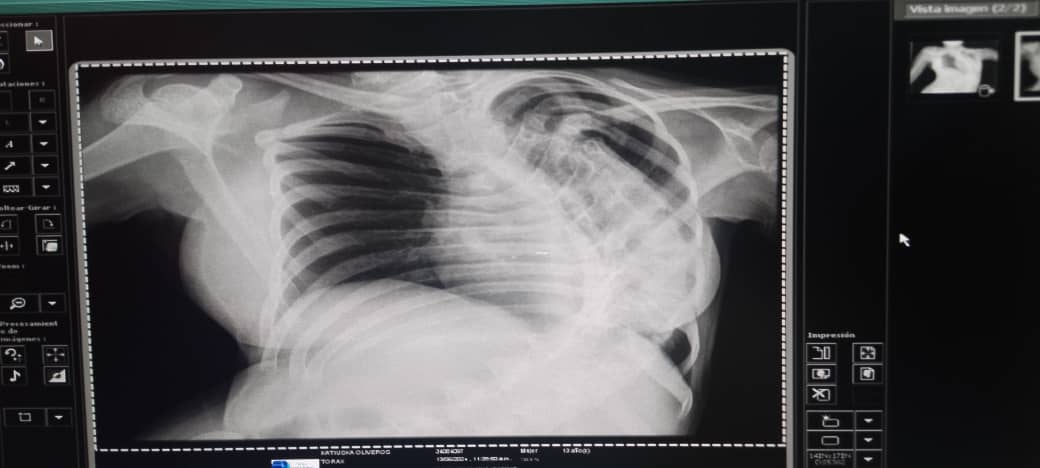

Katiuska Chiquinquirá Oliveros, una adolescente marabina de 13 años, nació con mielomeningocele, el tipo más grave de espina bífida, una afección que ocurre cuando la columna vertebral y la médula espinal no se forman adecuadamente.

La adolescente necesita realizarse con urgencia una cirugía de anclaje medular y artrodesis dorsolumbar, intervención que tiene como objetivo fusionar dos vértebras en la zona lumbar de forma permanente, de modo que no haya ningún movimiento entre ellas.